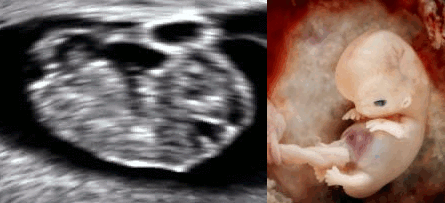

If you have seen an ultrasound2 before, you know that unborn babies at 10 weeks already look a lot like a tiny version of a born baby. Babies removed from ectopic pregnancies (such as the one pictured below, right3) also show what we look like during the earliest days of our lives.

Low resolution gif of an ultrasound of a baby moving at 9 weeks of gestation next to an ectopic pregnancy baby of the same age